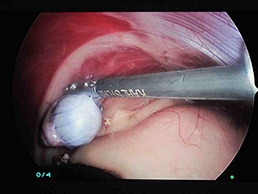

実際に腹腔鏡で確認したものもが下の写真です。

脾臓の裏の潜在精巣を超音波メスで切除し摘出しました。